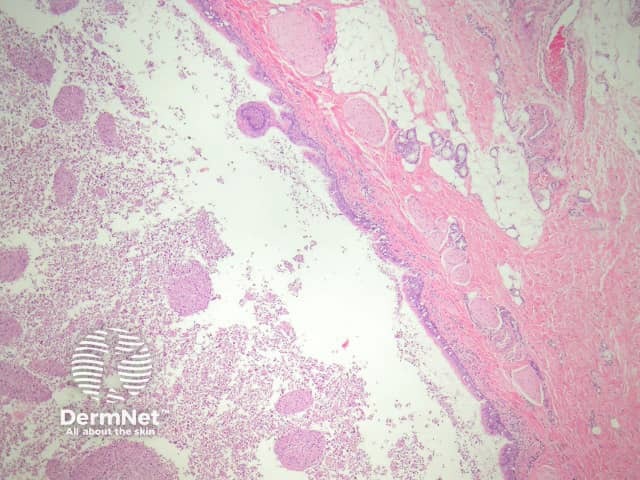

Bronchogenic cysts may be unilocular (figure 1) or multilocular. They may be located in the dermis or subcutis and occasionally drain into the overlying epidermis via a sinus. They are often filled with thick mucinous material and debris (figure 2).

Figure 1

Figure 2